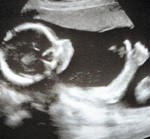

Baby Gives Mom "Thumbs Up" on Sonogram

A twenty-week old unborn child gave his mother a distinct "thumbs up" gesture during a sonogram:

Marie Boswell, 35, says friends and family have been amazed by her son's distinctive 'ok' sign in the 20-week scan taken at Wythenshawe Hospital.

Marie, of Wythenshawe, Manchester, said: "It's really funny, the thumb is so clear - we can't believe it.

"I have big hands but nothing on the scale of his - he looks like he's wearing boxing gloves! We're thinking he might make a good goalkeeper.